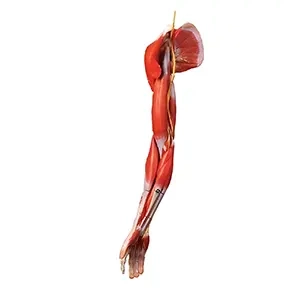

مولاژهای آناتومیک:

- مولاژهای کامل بدن: مدلهایی که تمام بخشهای بدن انسان را به طور کامل و تفصیلی نمایش میدهند.

- مولاژهای اعضای خاص: مدلهایی که بر روی اعضای خاص بدن مانند قلب، کبد، ریهها یا کلیهها تمرکز دارند.

مولاژهای آناتومیکی: این دسته شامل مدلهای بدن کامل یا بخشهای خاص مانند قلب، ریهها، سیستم گوارش و غیره است. این مولاژها به درک بهتر ساختار و عملکرد اعضای بدن کمک میکنند.

ماکتهای آناتومیکی: این ماکتها نمایانگر ساختارهای مختلف بدن انسان از جمله اسکلت، عضلات، سیستم عصبی و سیستمهای داخلی هستند. این ماکتها ممکن است به صورت کامل یا بخشهای خاصی از بدن مانند قلب، ریهها و کبد طراحی شوند.

- ماکتهای آناتومیکی: برای نمایش جزئیات آناتومی بدن، از جمله اسکلت، عضلات، و اعضای داخلی.

۱. مولاژهای آناتومیکی

این مولاژها برای مطالعه و درک ساختارهای مختلف بدن انسان طراحی شدهاند. شامل موارد زیر هستند:

- مولاژهای استخوانی: شبیهسازی دقیق اسکلت انسان، مناسب برای آموزش آناتومی استخوانها.

- مولاژهای عضلانی: نمایش عضلات اصلی و گروههای عضلانی بدن.

- مولاژهای سیستمهای داخلی: مانند سیستم گردش خون، تنفسی و گوارشی، برای مطالعه و آموزش عملکرد این سیستمها.